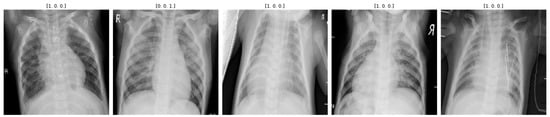

3.2.2. Data Augmentation to Control Class Imbalance